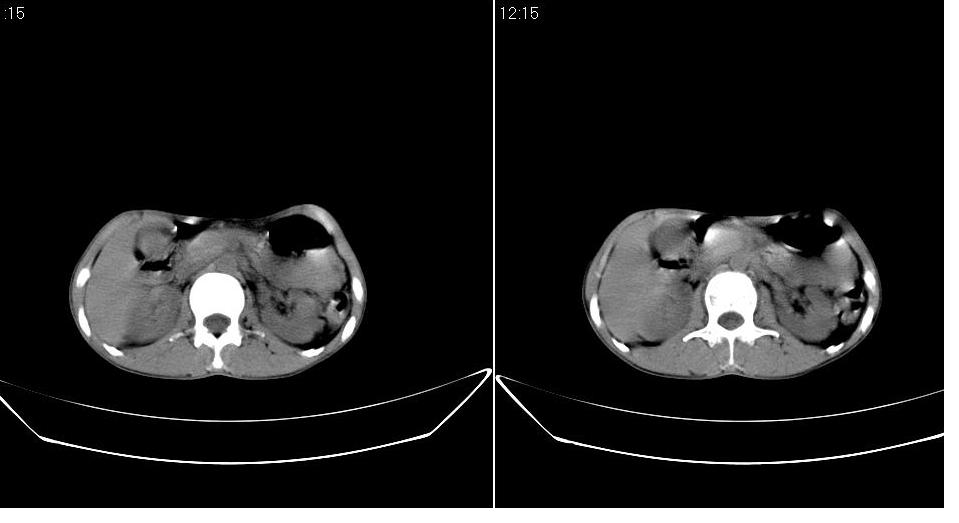

标题: CT19774:上腹部CT平扫

女 28岁,急诊,腹疼一天。

胰体尾部较胖,是不是有胰腺炎?

胆囊底部囊壁增厚,考虑胆囊炎。胰腺改变考虑为部分容积效应。

不排除胰腺炎可能;建议查血尿淀粉酶。

图像不是很清楚,胰腺炎?